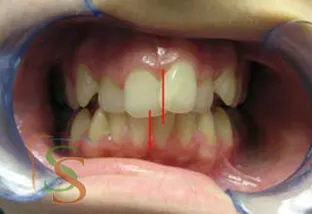

Vuoi vedere come una terapia si sviluppa nel tempo?